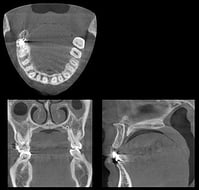

手術の際も歯科用CTによる正確な画像診断や微細な病変も見えるマイクロスコープ、生体にやさしい修復剤であるプロルート(MTA)などを使用することによってさらに成功率の大幅な向上と良好な予後が期待されます。